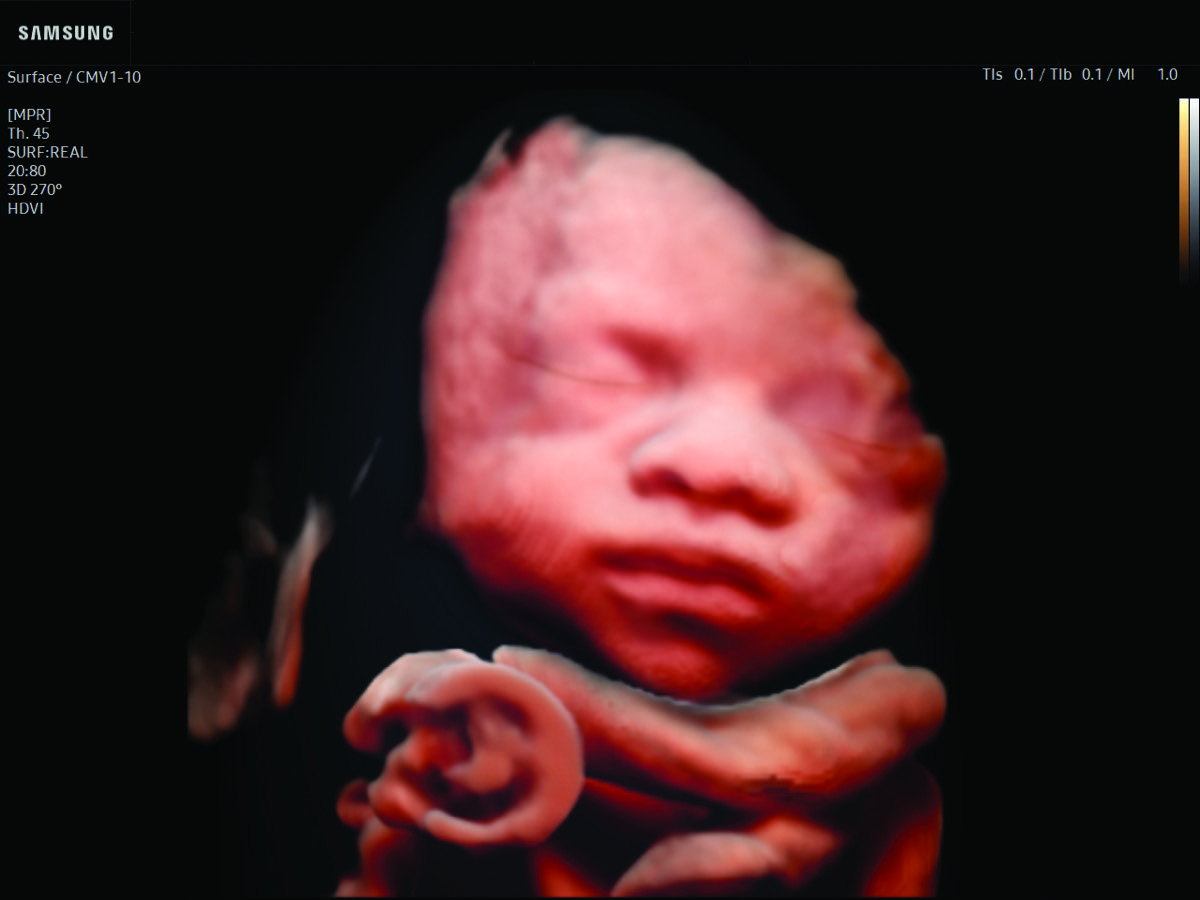

Comprehensive, advanced and expert MFM care for high-risk pregnancies

- Fetal anomalies